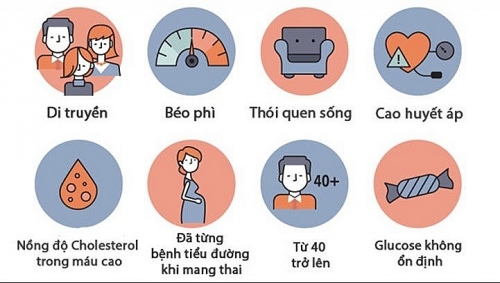

Nguyên nhân tiểu đường

Nguyên nhân tiểu đường là gì? Cách chữa bệnh tiểu đường để không gặp các biến chứng nguy hiểm?